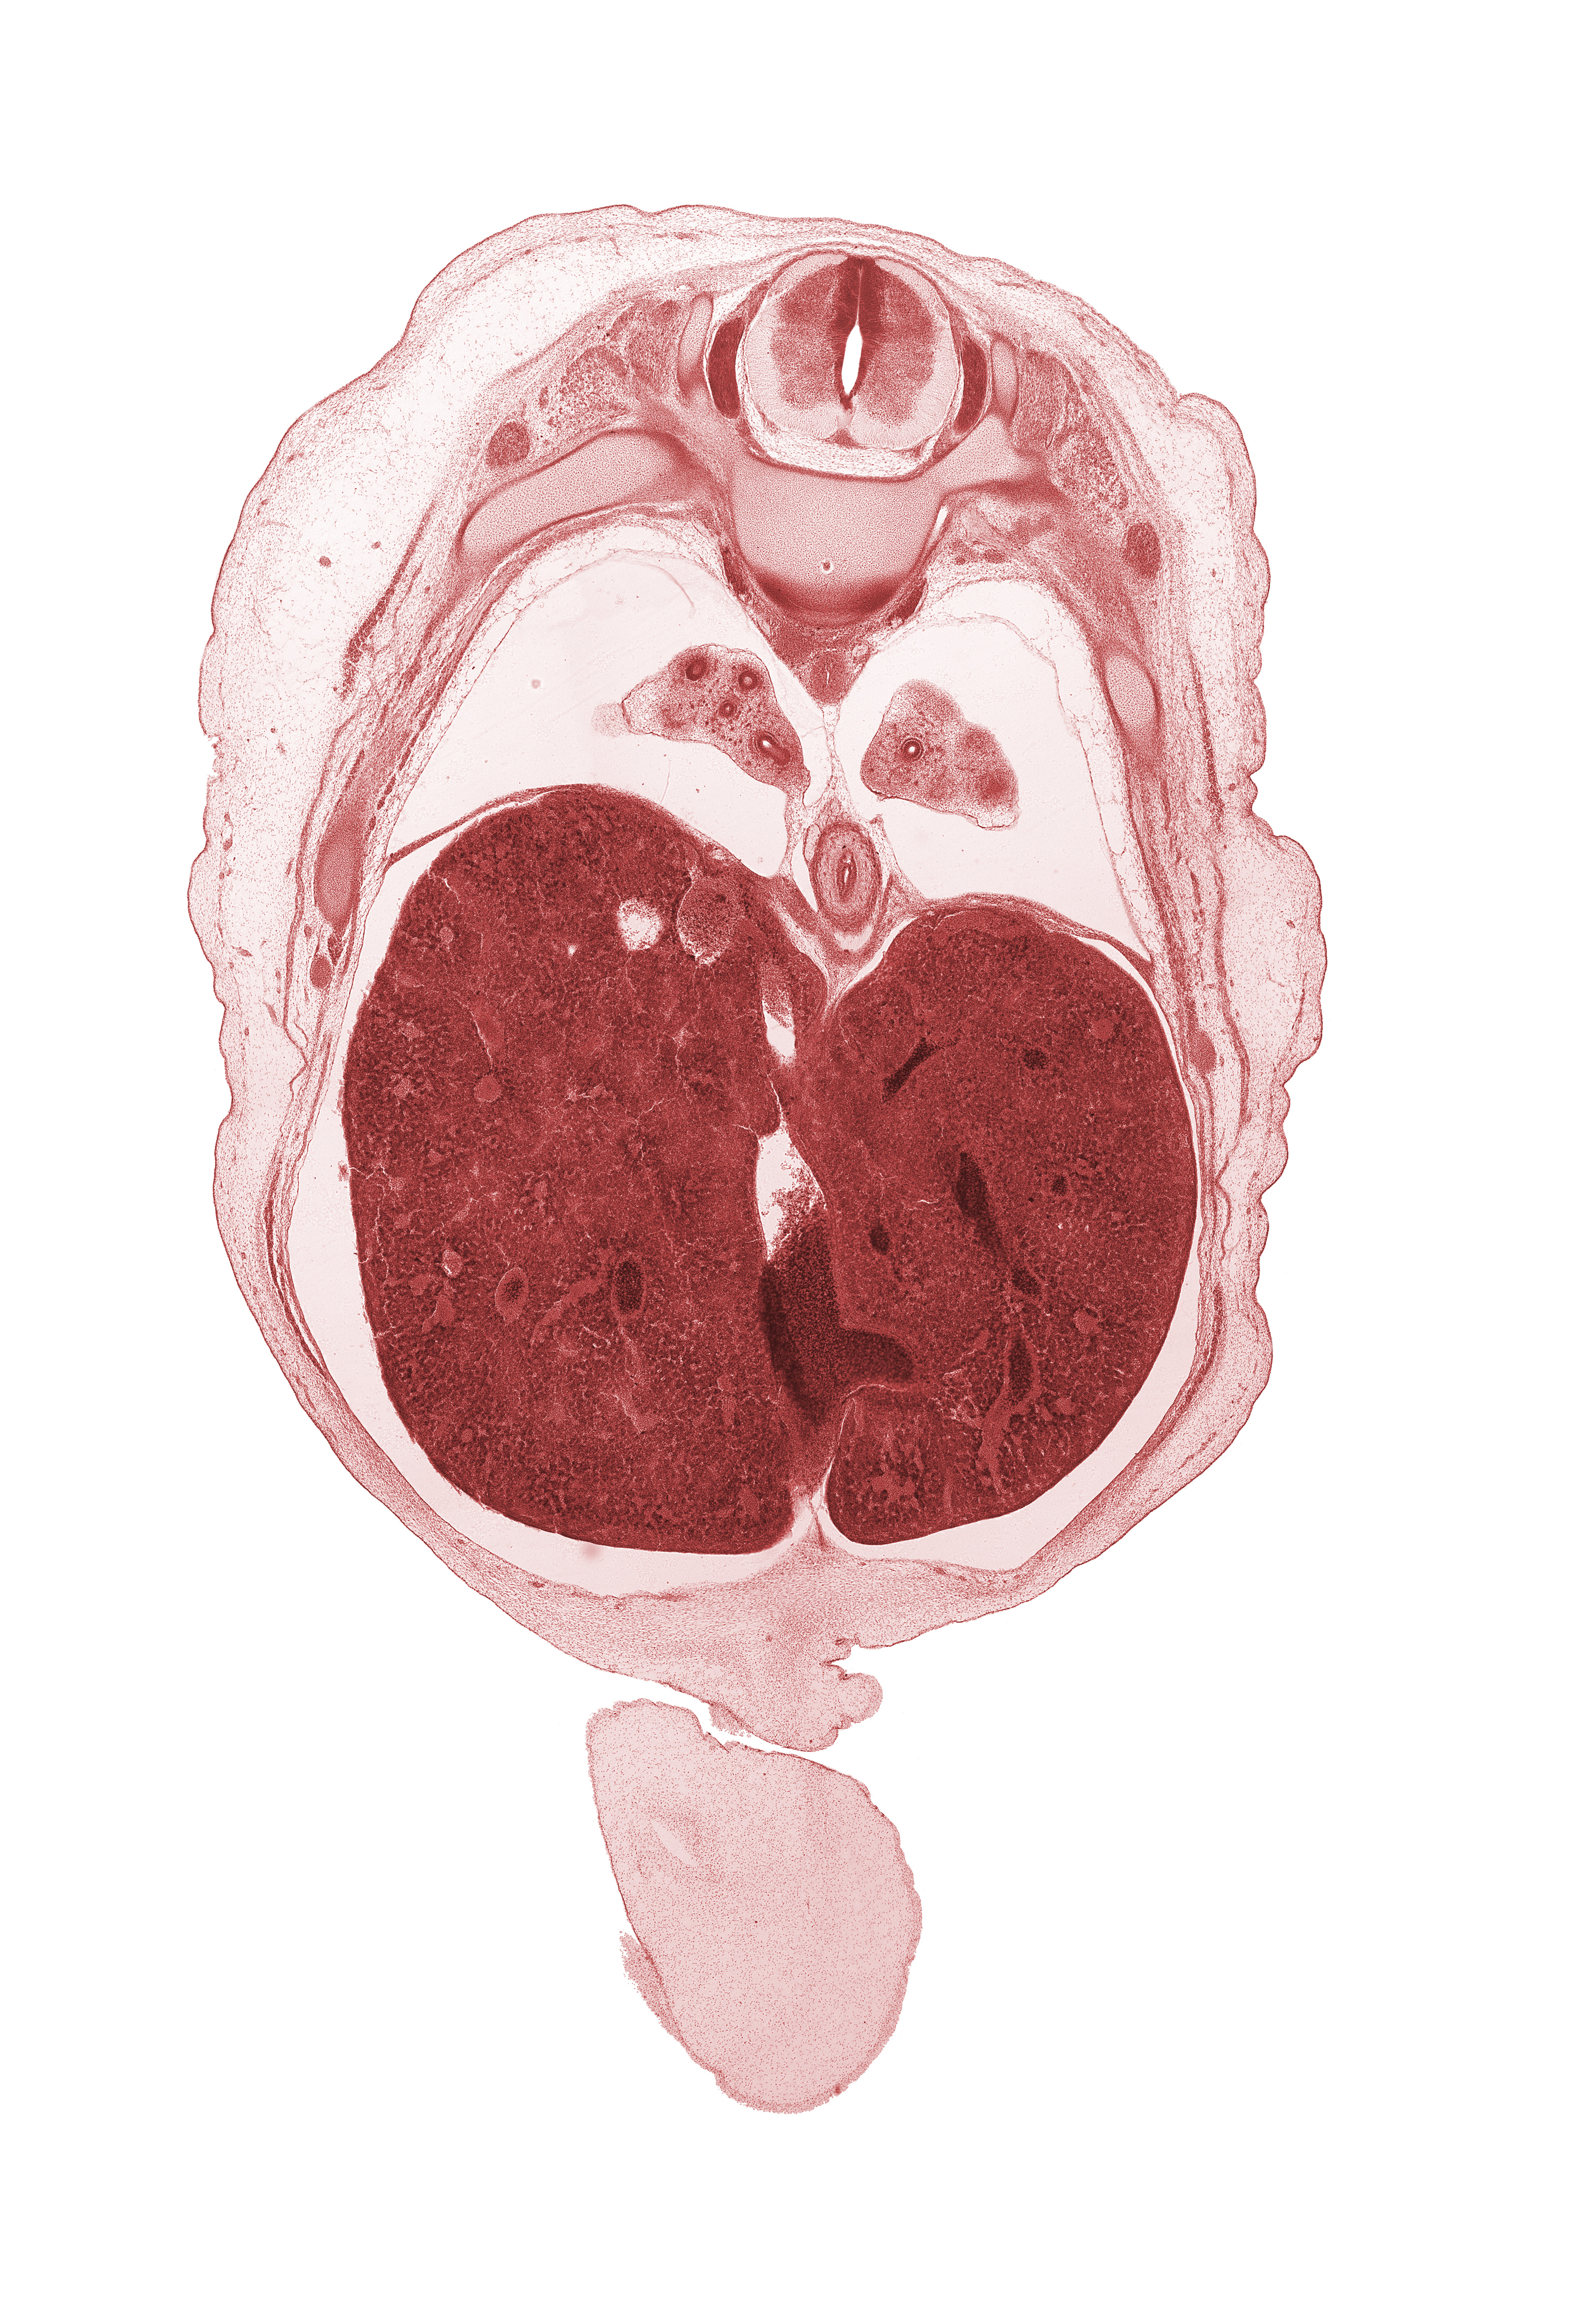

Carnegie Embryo #462 | Location: 4-02-03

Keywords: T-8 intercostal nerve, T-8 spinal ganglion, T-8 spinal nerve, afferent hepatic vein, amnion on surface of umbilical cord, azygos vein, diaphragm, ductus venosus, esophagus endoderm, falciform ligament, inferior vena cava (hepatic part), left lobe of liver, lower lobe of left lung, lower lobe of right lung, pleural cavity, rib 9, right lobe of liver, sympathetic trunk

Source: The Virtual Human Embryo.